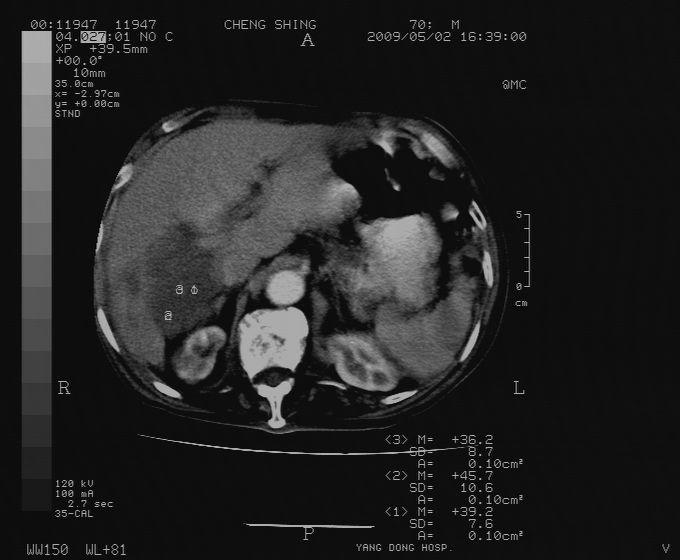

标题: CT19743:男70岁,肺部疾病入院,B超发现肝右叶占位,CT [打印本页]

标题: CT19743:男70岁,肺部疾病入院,B超发现肝右叶占位,CT

肝表面塌陷,病灶周围有子灶,前面较大子灶强化符合肝癌表现,考虑肝癌肝转移可能性大.

1)考虑肝癌并肝内转移。2)少量腹水。3)双侧胸腔积液。

1)考虑肝癌并肝内转移。2)少量腹水及双侧胸腔积液。3)椎体退变。